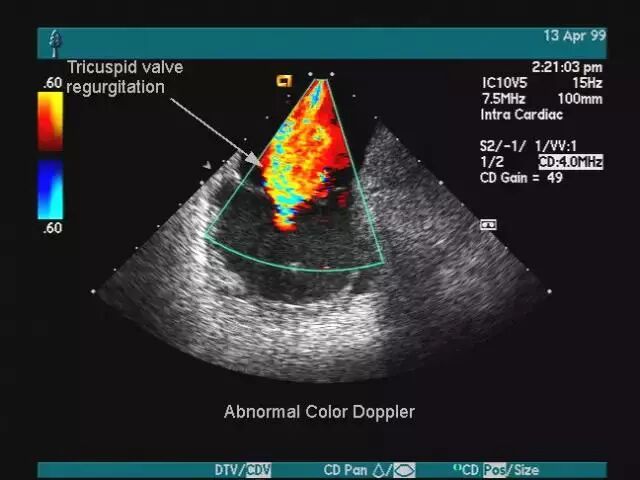

医生可以在显示器上观测到的图像以红蓝两色为主,面向探头的呈现红色,反之为蓝色。

这种技术能够观测到器官内部血液流动情况,而血流与疾病的性质有密切关系。

一句话,打开多普勒功能医生可以看到红蓝色的血流情况,而关上它,就是普通的黑白B超。

所以大家别再以为彩超就是彩色电视机一样,能看到彩色的脏器,彩超也仅仅只有红蓝两色而已。